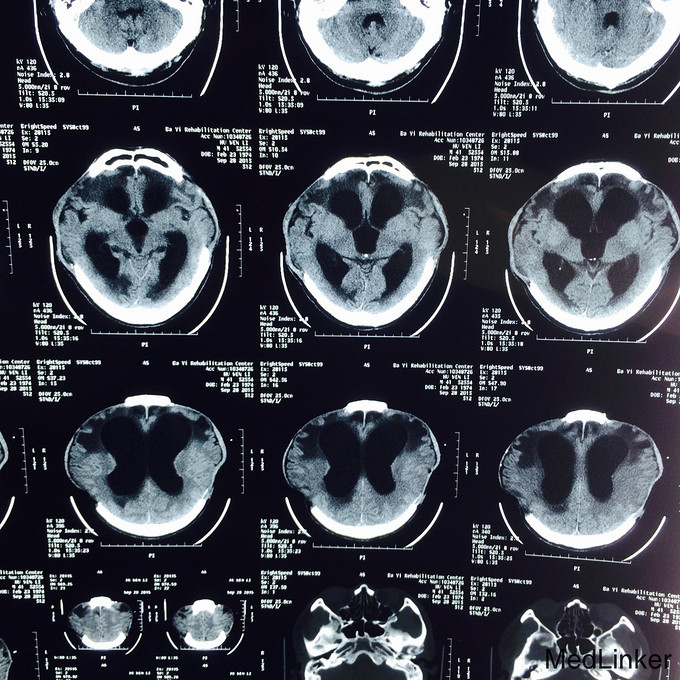

患者,男,41岁,因“脑外伤后意识障碍4月”入院。 现病史: 患者于3月前因高空坠落伤后,出现意识障碍,遂送当地医院,行双侧颅骨去骨瓣减压,血肿清除术,气管切开术;2+月前开始能睁眼,右上肢偶能执行一些简单指令动作,如握手;不能言语,四肢运动功能障碍,左侧为重。大小便障碍,为进一步促醒,康复治疗,遂转本院继续治疗。既往史:既往体健,无重大疾病病史。

入院查体:气管切开,自带鼻饲管,生命体征稳定:脉搏 70次/分,血压121/71mmHg;Glasgow昏迷评分9分,最小意识状态;双侧颅骨缺如;四肢肌张力增高,肌力1-2级,左上肢肘关节活动受限。 辅查:血常规、肝肾功、凝血、电解质、血脂、血糖均正常;头颅MRI(2015.09.17)示:双侧额颞叶及右侧枕顶叶片状低密度影;交通性脑积水;双侧颞额顶骨部分缺如,相邻脑组织膨出,多系术后改变;头颅MRI(2015.09.28)示:与前面的片子比较,变化不大;

诊断:重型颅脑损伤 双侧额叶脑挫裂伤;双侧额颞顶部硬膜下血肿;脑疝形成;最小意识状态。 入院后治疗上积极给以神经营养、床旁康复治疗,高压氧治疗20天促醒;预防肺部感染;预防癫痫发作;

患者病情好转缓慢,2周前强直阵挛发作一次;影像资料提示颅内情况并未明显改善。请神经外科会诊后,建议作脑脊液侧脑室腹腔分流术。对于有脑积水的患者,不排除越早行脑脊液分流术,意识障碍恢复的时间就越短,效果就越好!另外,高压氧治疗方面,怎样发挥出最佳的治疗效果?